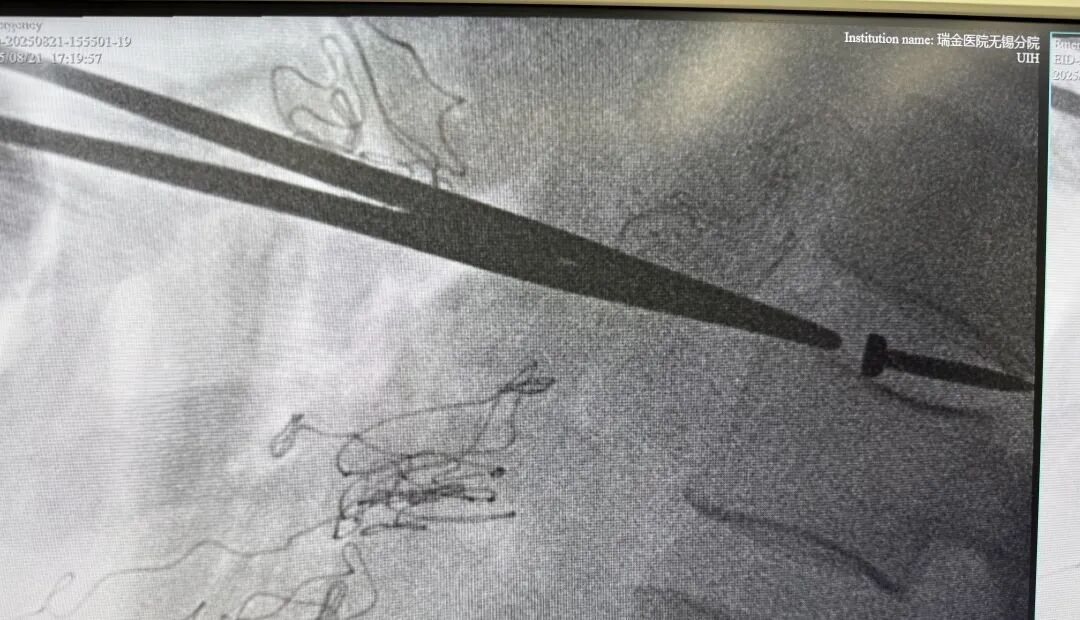

CT影像检查显示

其腰椎间盘里卡竟着一枚

长约3cm的金属钉!

据医生介绍,钉子从腹壁到椎间盘,“走”了约40cm,疑似穿了多个腹腔脏器!

医生称,此枚金属钉依次刺穿腹壁、肝脏左叶、胃壁、结肠系膜、十二指肠、后腹膜,最终嵌插于腰椎间盘内,若处理不好很可能术后出现胆瘘、肠瘘等问题。经过3小时的手术,张师傅体内的钉子终于被取出,且取出后确认是一枚尾部有火药的工程钉。

医生表示,虽然刺穿多个脏器,imtoken钱包官方app下载不过幸运的是,钉子穿过腹部时,并未伤及各大血管,并且正好钉在椎间盘之间,未伤及脊髓。